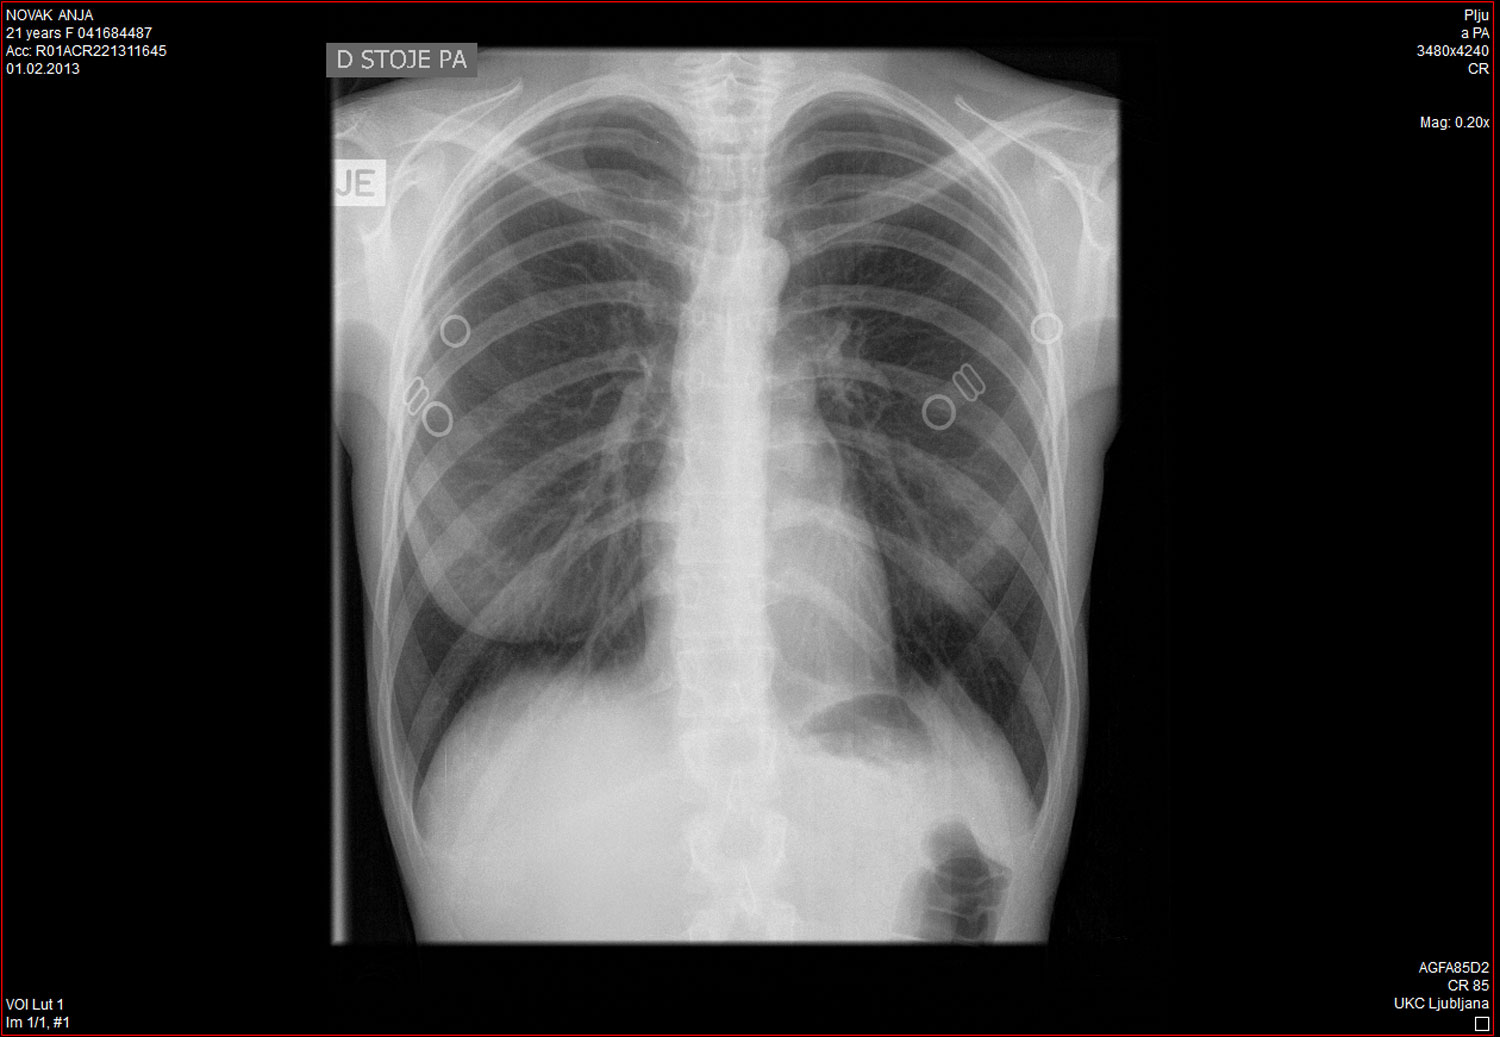

Foto: rentgen na UKC Ljubljana, potem, ko si je Anja med predstavo zlomila rebro

Posneto na koncertu v Pritličju oktobra 2016. Komad je nastal kot material za možno predstavo med študijem Brechta in vauefekta na akademiji dve leti prej. Ostaja večno nepopoln.